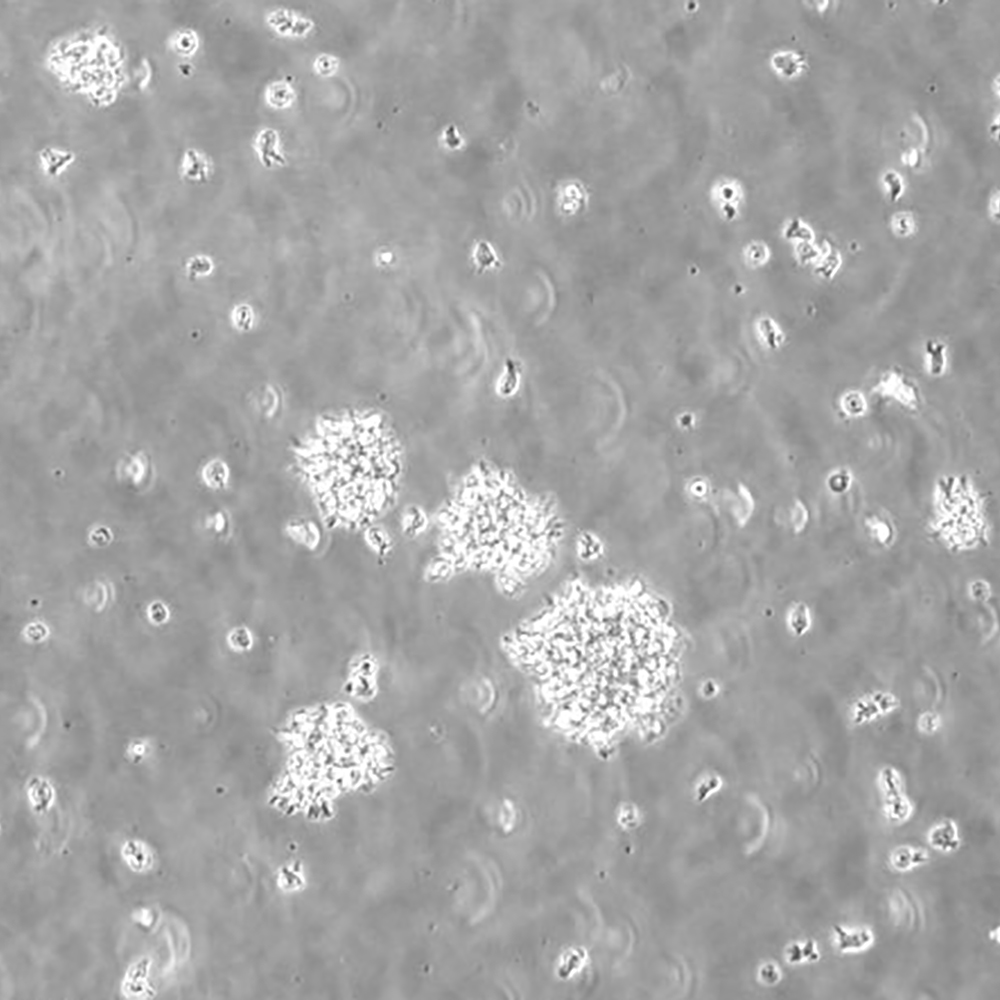

CCRF-SB

中文名稱 人急性T淋巴細胞白血病細胞

組織來源 急性T淋巴細胞白血病;男性

生長特性 懸浮